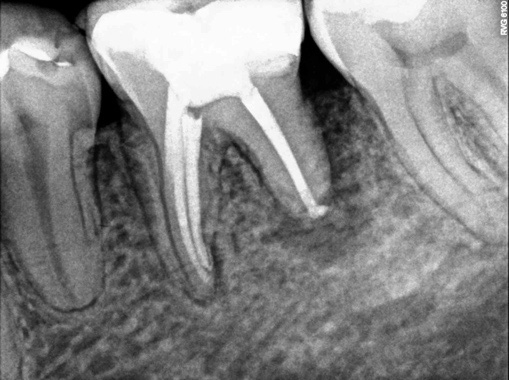

After this period there was remission of signs and symptoms. Bio-C TEMP was removed with saline solution associated with CUI (Continuous Ultrasound Irrigation) and a new irrigation with 5.25% Sodium Hypochlorite. For the root canal filling, the bioceramic-based sealer (Bio-C Sealer) was used (Figures 3 and 4A and 4B).

Figure 4: Final radiograph (B)